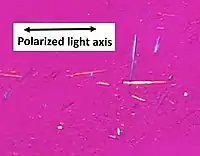

Polarized light microscopy is commonly used in biological tissue, as many biological materials are linearly or circularly birefringent. Collagen, found in cartilage, tendon, bone, corneas, and several other areas in the body, is birefringent and commonly studied with polarized light microscopy.[11] Some proteins are also birefringent, exhibiting form birefringence.[12]

Birefringence is utilized in medical diagnostics. One powerful accessory used with optical microscopes is a pair of crossed polarizing filters. Light from the source is polarized in the x direction after passing through the first polarizer, but above the specimen is a polarizer (a so-called analyzer) oriented in the y direction. Therefore, no light from the source will be accepted by the analyzer, and the field will appear dark. Areas of the sample possessing birefringence will generally couple some of the x-polarized light into the y polarization; these areas will then appear bright against the dark background. Modifications to this basic principle can differentiate between positive and negative birefringence.

For instance, needle aspiration of fluid from a gouty joint will reveal negatively birefringent monosodium urate crystals. Calcium pyrophosphate crystals, in contrast, show weak positive birefringence.[17] Urate crystals appear yellow, and calcium pyrophosphate crystals appear blue when their long axes are aligned parallel to that of a red compensator filter,[18] or a crystal of known birefringence is added to the sample for comparison.